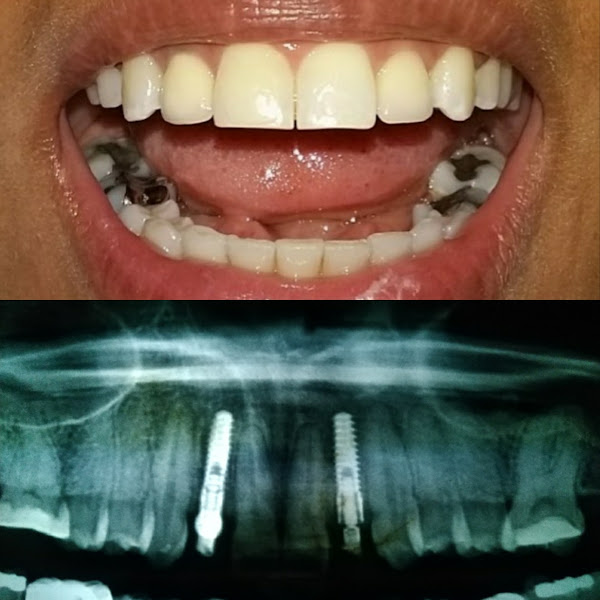

“Experiência única pra vida toda! Cheguei no consultório cheia de incertezas, medos traumas. A equipe mim acolheu de uma forma extraordinária . Dr João o melhor de todos que já passei. Lembro que na minha primeira consulta cheguei lá desacreditada querendo extrair todos os meus dentes rsrsrs, pq eu já tinha feito procedimentos em outro consultório e não obtive bons resultados. E ele com toda paciência mim explicou a importância de continuar com os meus dentes. E na base de muita conversa entendi a importância de manter os dentes e tratar-los . Foi assim que resolvir fazer os implantes. Fiz extrações e 04 implantes de muito sucesso. Um dentista fora do sério, que durante o procedimento muito cuidadoso, preoculpado sempre conversando perguntando se estava sentindo dores, dias depois do procedimento ele com o mesmo cuidado e preoculpacão mandava mensagem prá saber como eu estava. Ele é diferenciado o que acho incrível é a forma que ele acolhe os pacientes e ele demostra que o que faz é com amor. Mim ajudou muito facilitando para que eu fizesse o tratamento sou muito grata a Deus por ter colocado ele na minha vida. Fiz procedimentos com outros dentista do consultório mais com Dr. João eu mim sinto segura confio e acato tudo que ele dizer que é melhor pra mim, ainda estou em tratamento. Hojé ele não é só meu dentista ele é meu amigo e não largo mais pra nada. Enfim super indico.”